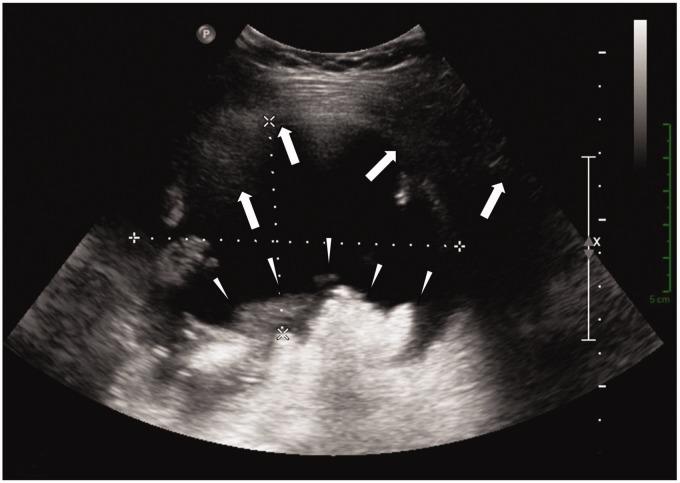

We present the case of a 53-year-old woman with a known history of hereditary multiple exostosis disease referred for further imaging work-up after ultrasound and computed tomography leading to the suspicion of malignant transformation of an osteochondroma (exostosis) located on the posteromedial aspect of the right proximal femur. Imaging examinations suggested an ischiofemoral impingement resulting in a secondary bursitis associated with the development of an internal lipoma arborescens. This rare association explained the complexity of the diagnosis. Magnetic resonance imaging (MRI) played a key role in correctly identifying this benign complication of the osteochondroma and in distinguishing those observations from a secondary exostotic chondrosarcoma. MRI findings were subsequently confirmed at surgery and pathological examination.

我们报告了一例53岁女性病例,该患者有遗传性多发性骨软骨瘤病病史。在超声和计算机断层扫描后,怀疑位于右股骨近端后内侧的骨软骨瘤(外生骨疣)发生恶变,遂进行进一步影像学检查。影像学检查提示坐骨股骨撞击,导致继发性滑囊炎,并伴有内部树状脂肪瘤的形成。这种罕见的关联解释了诊断的复杂性。磁共振成像(MRI)在正确识别骨软骨瘤的这种良性并发症以及将这些表现与继发性外生骨疣性软骨肉瘤区分开来方面发挥了关键作用。MRI结果随后在手术和病理检查中得到证实。